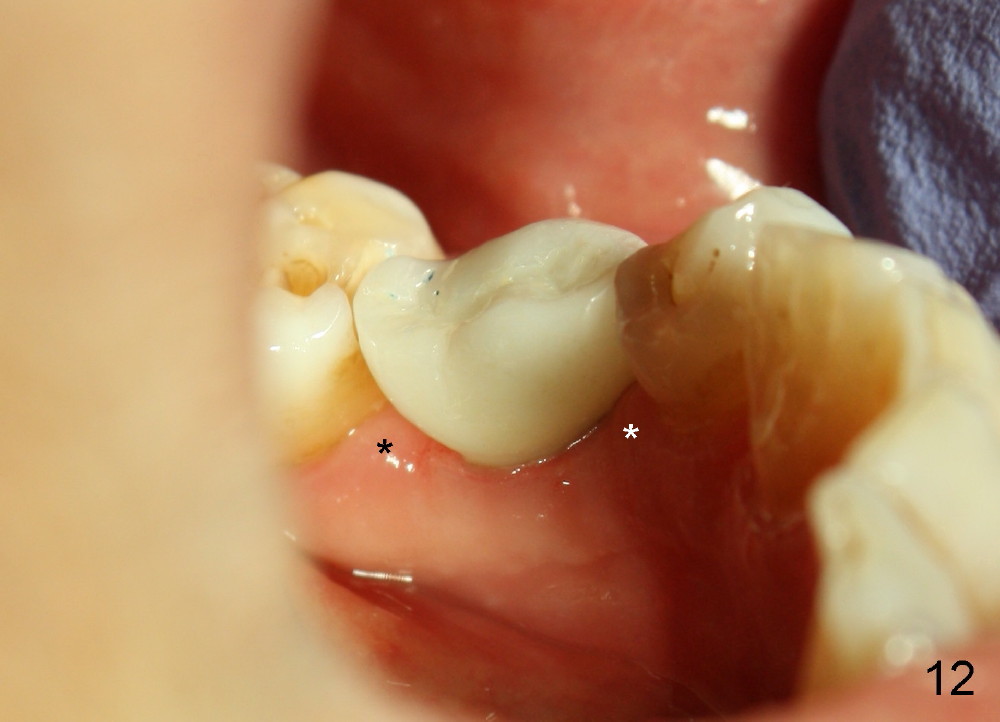

When the crown is bonded, the papillae (*) look basically normal lingually (Fig.12) and buccally (Fig.13).